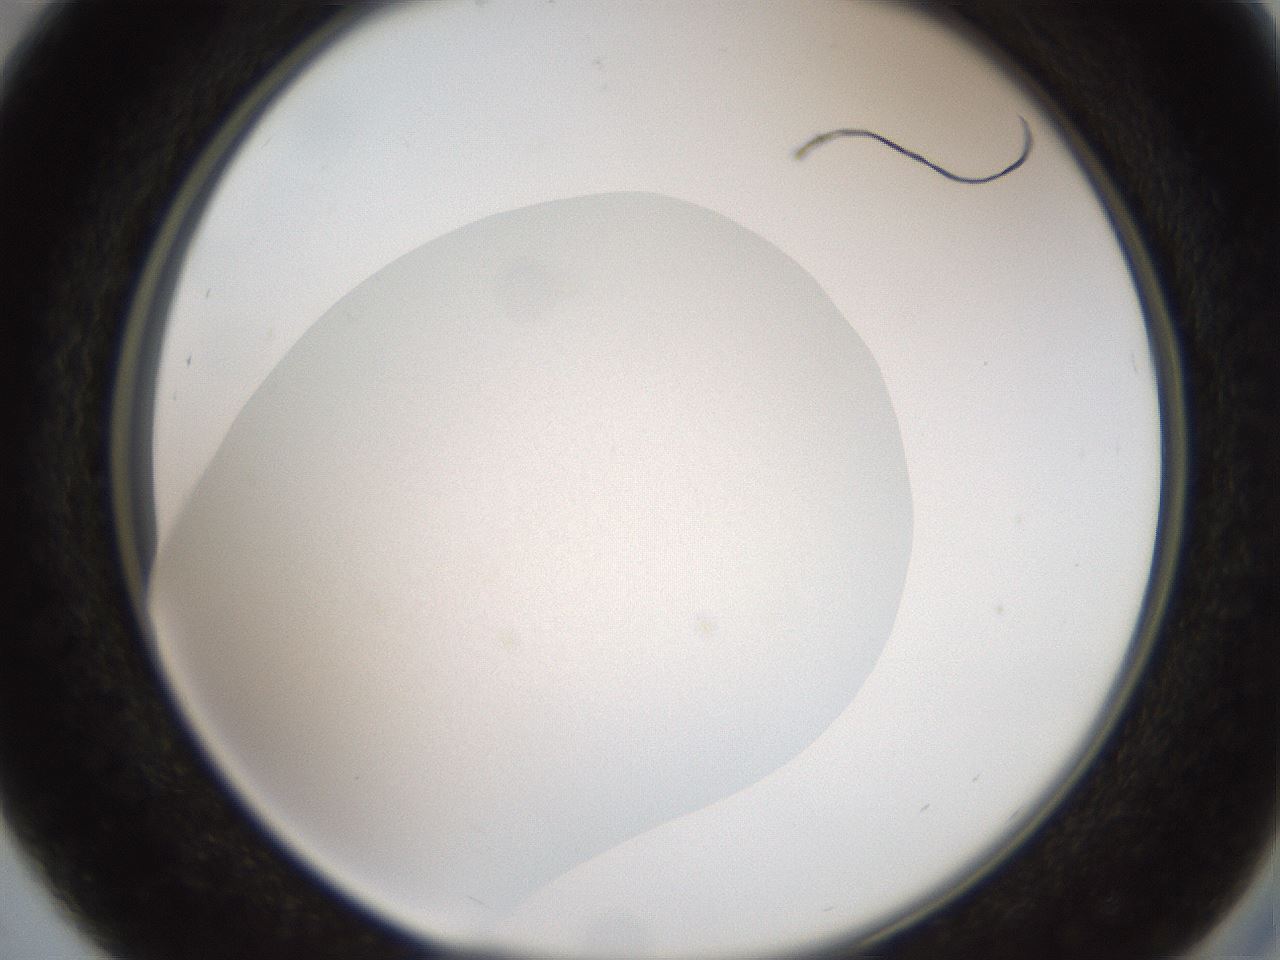

folderID618_plateID1618_batchID6746_wellNum29_profileID1_d2_r107633_ef.jpg